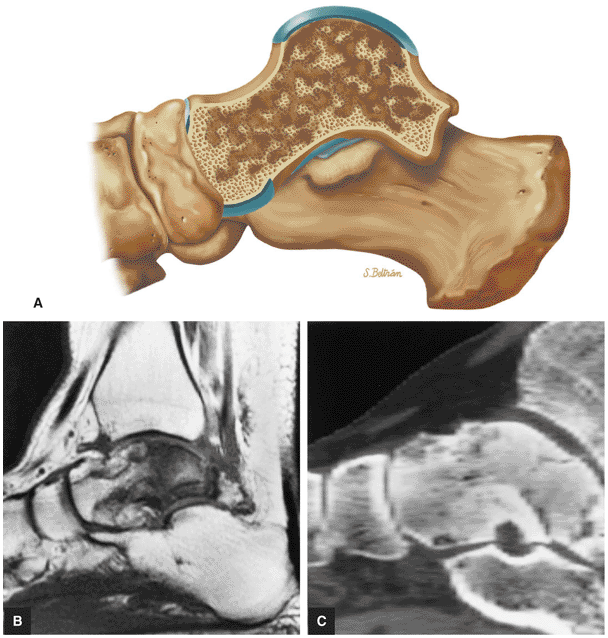

FIGURE 5.92 ● Anterolateral and posteromedial locations of osteochondral lesions of the talus. The lateral lesions tend to be shallower and wafer-shaped, whereas the medial lesions are deeper and cup-shaped.

FIGURE 5.93 ● Medial cup-shaped osteochondral lesion (OLT). Medial OLTs are more common than lateral ones, but lateral lesions are associated with trauma in over 90% of cases. Medial lesions are ascribed to trauma in about 70% of cases. Coronal FS PD FSE image.

FIGURE 5.94 ● Lateral OLT with intact overlying chondral surface. Subchondral trabecular fracture and adjacent marrow edema are demonstrated on a coronal T1-weighted image (A). Mid-lateral talar dome location is shown with a cross-sectional area of reactive marrow edema. The edema associated with OLT should not be misinterpreted and result in overestimation of the area of trabecular bone involved. Coronal T1-weighted image. (B) Coronal FS PD FSE image. (C) Axial FS PD FSE image. (D) Color illustration with the capsule cut and the tibia and fibula reflected. Compression-type OLT corresponding with an area of subchondral trabecular compression in a stage I lesion.